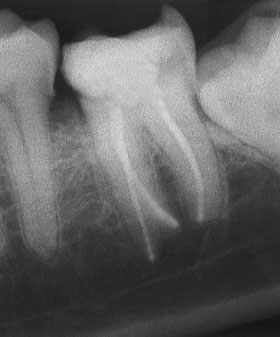

При добре проведено ендодонтско лечение кореновият канал е запълнен точно до стеснението, разположено на 1 - 1.5 мм. от края на канала - т.нар. физиологично стеснение. Не бива да остава незапълнена част от канала. Много често се получава припресване на канлопълнежното средство извън канал на зъба, в тъканите около корена.

Рентгенографии на добре пролекувани зъби

При наличие на огнище на възпаление около корените на зъба добре проведеното лечение води до изчезване на изменението. На снимката долу едва една седмица след пролекуване на каналите се наблюдава известна редукция на патологичния процес. За период от 6 месеца до 2 години е възможно да се наблюдава пълен оздравителен процес.